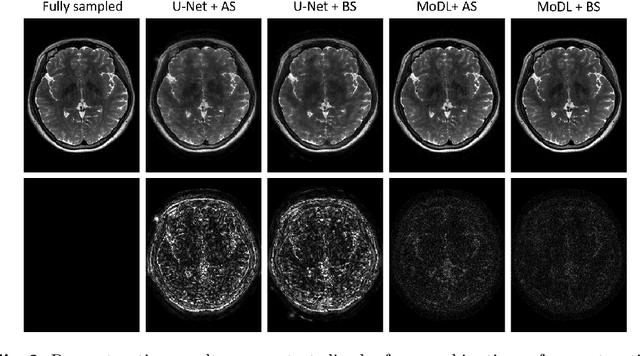

The previously established LOUPE (Learning-based Optimization of the Under-sampling Pattern) framework for optimizing the k-space sampling pattern in MRI was extended in three folds: firstly, fully sampled multi-coil k-space data from the scanner, rather than simulated k-space data from magnitude MR images in LOUPE, was retrospectively under-sampled to optimize the under-sampling pattern of in-vivo k-space data; secondly, binary stochastic k-space sampling, rather than approximate stochastic k-space sampling of LOUPE during training, was applied together with a straight-through (ST) estimator to estimate the gradient of the threshold operation in a neural network; thirdly, modified unrolled optimization network, rather than modified U-Net in LOUPE, was used as the reconstruction network in order to reconstruct multi-coil data properly and reduce the dependency on training data. Experimental results show that when dealing with the in-vivo k-space data, unrolled optimization network with binary under-sampling block and ST estimator had better reconstruction performance compared to the ones with either U-Net reconstruction network or approximate sampling pattern optimization network, and once trained, the learned optimal sampling pattern worked better than the hand-crafted variable density sampling pattern when deployed with other conventional reconstruction methods.